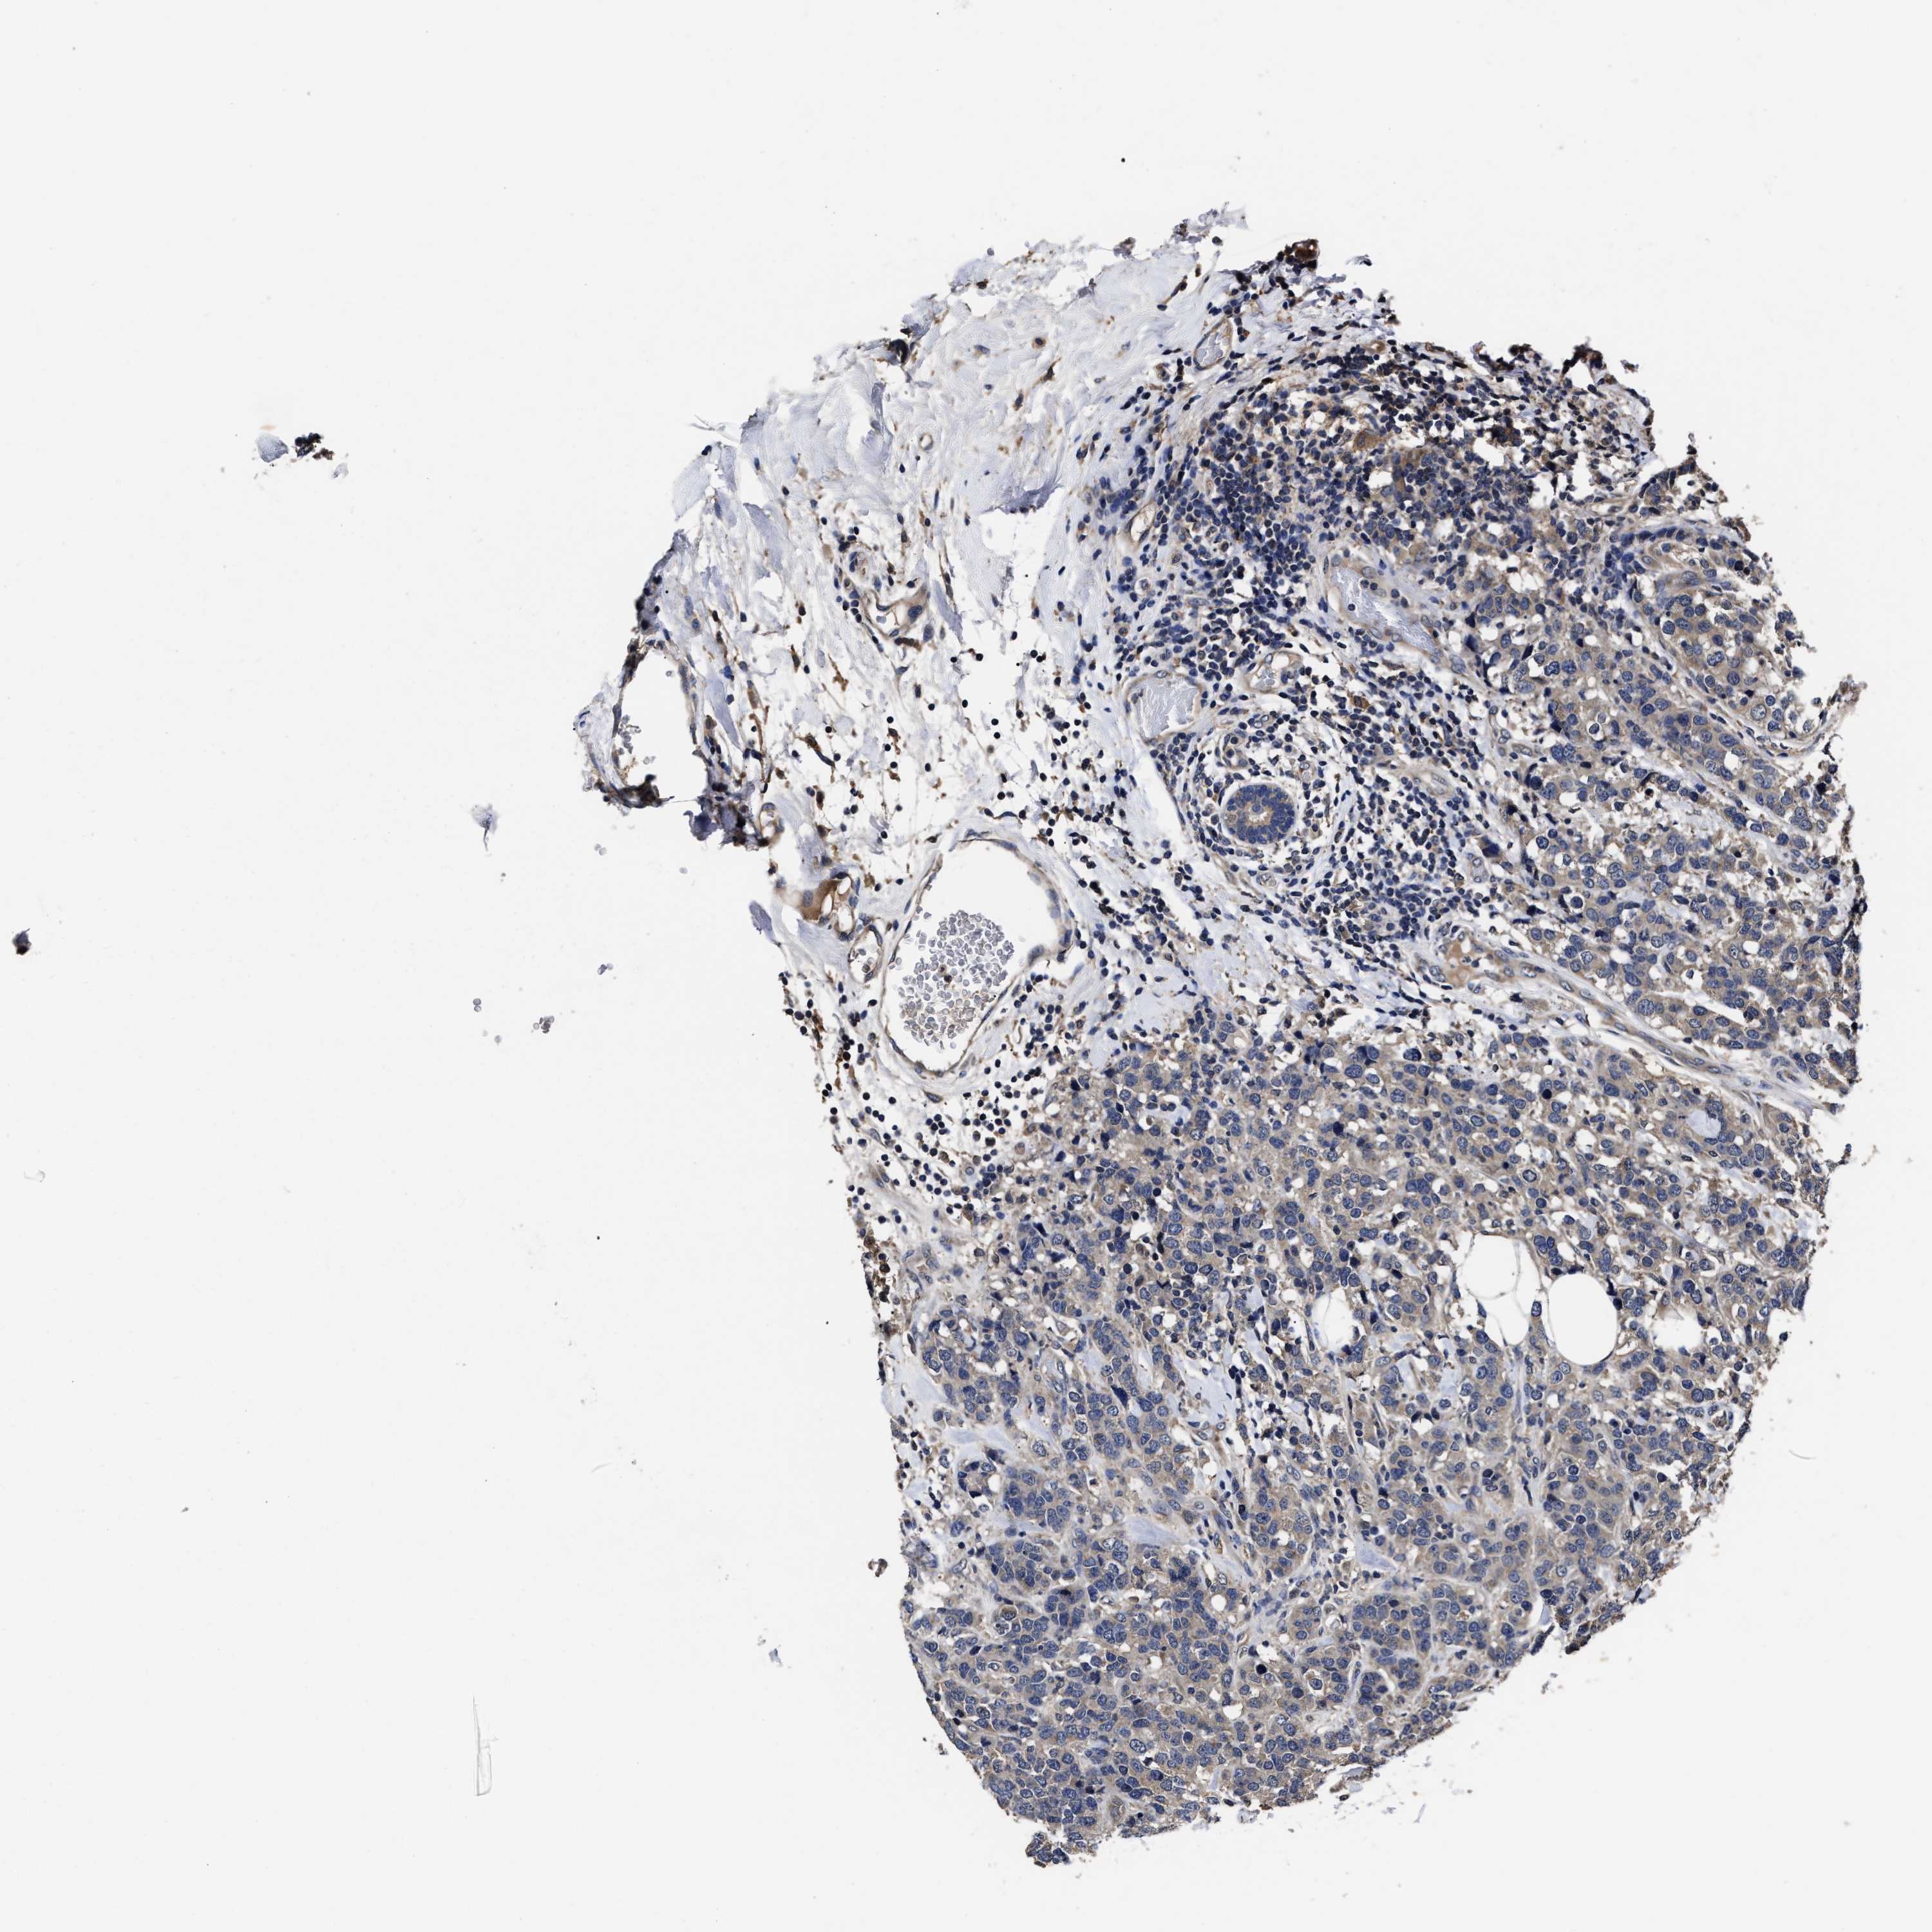

CANCER BREAST CANCER Show tissue menu

Breast cancer

Human cancer